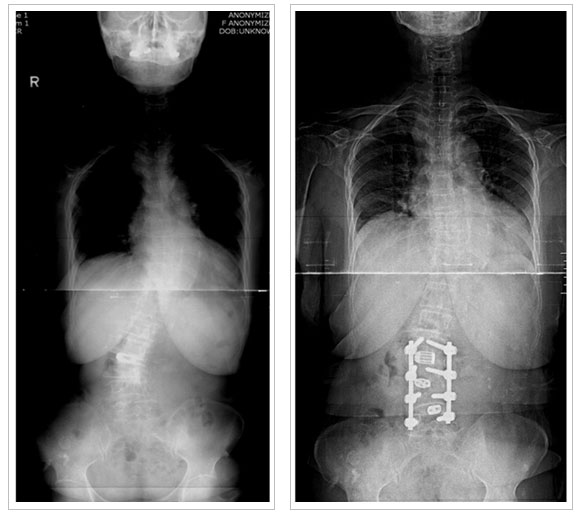

2)

¼ö¼úÀû Ä¡·á

| |

- ¼ºÀå±âÀÇ

45µµ ÀÌ»óÀÇ ¸¸°î

- ¼ºÀåÀÌ ³¡³ 50µµ ÀÌ»óÀÇ ¸¸°î

* ¼ö¼ú¹ý

- ÈĹ汳Á¤ ¹× ÈĹæ±â±â¼ú : ôÃß°æ ³ª»ç¸ø

°íÁ¤¼ú

- Àü¹æ±³Á¤ ¹× Àü¹æ±â±â¼ú : ÃÖ¼ÒÀý°³¹æ½Ä,

³»½Ã°æ ¹æ¹ý

- ÀüÈĹ汳Á¤ ¹× ÈĹæ±â±â¼ú

- °ßÀÎ ÈÄ ÈĹ汳Á¤¼ú

2) ÅðÇ༺ ôÃßÃø¸¸Áõ

: 78¼¼/¿©ÀÚ

ÁÖ·Î ³ªÀ̰¡

µé¸é¼ ¹ß»ýµÇ¸ç ôÃß°ü ÇùÂøÁõÀÌ ÁÖÁõ»ó

Ä¡·á´Â ôÃß°ü ÇùÂøÁõ¿¡ ´ëÇÑ Ä¡·á¿Í º¯Çü±³Á¤À» µ¿½Ã¿¡ ½Ç½ÃÇÔ